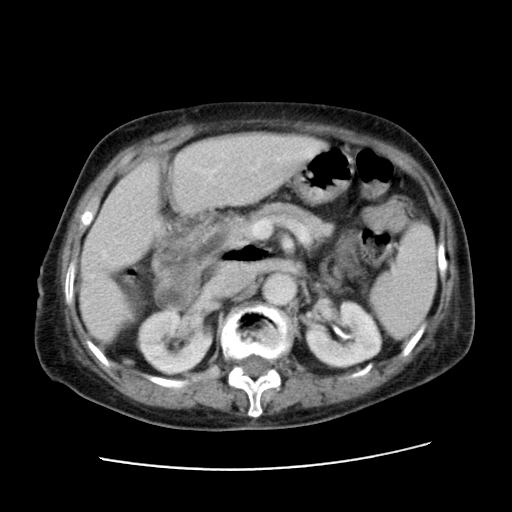

女,77.无不适

肝脏变异、异位胆囊,肝右叶肝内胆管结石并肝内胆管扩张。

肝右叶肝内胆管结石并肝内胆管扩张。

肝右叶肝内胆管结石并肝内胆管扩张

胆总管扩张

肝右叶肝内胆管结石并肝内胆管扩张。胆总管下段梗阻,考虑壶腹部占位。

右侧肝内胆管局限性扩张,其内密度不均匀,扩张的胆管壁增厚,考虑肝内胆管炎合并结石可能性大

肝右叶肝内胆管结石并肝内胆管扩张。胆总管下段梗阻,考虑壶腹部占位。支持